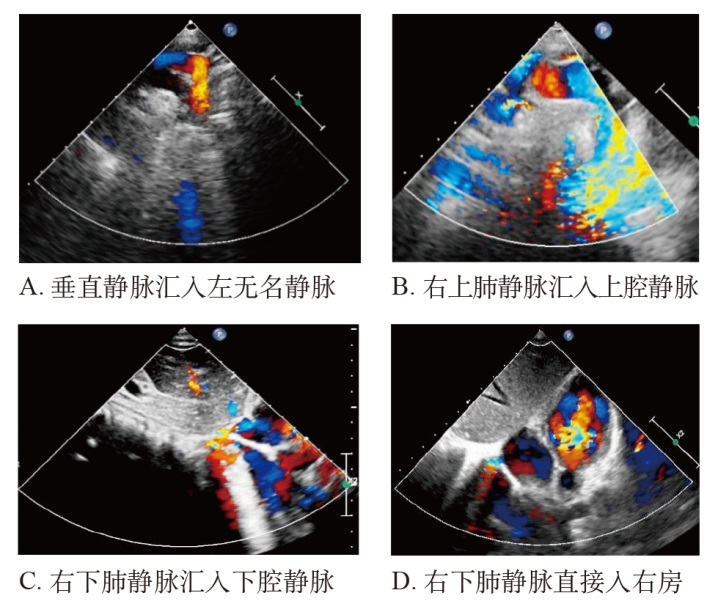

| [3] | 张颖, 弓文清, 胥盼, 等. 房间隔完整的肺静脉异位引流超声影像特征分析[J]. 中国超声医学杂志, 2020, 36(10): 895-898. |

| Zhang Y, Gong WQ, Xu P, et al. Analysis of Ultrasound Imaging Features of Anomalous Pulmonary Venous Drainage with Intact Septum[J]. Zhongguo Chaosheng Yixue Zazhi, 2020, 36(10): 895-898. | |

| [9] | 尹楠迪, 白洋, 程艳彬, 等. 部分性肺静脉异位连接的超声心动图评估[J]. 中国临床医学影像杂志, 2023, 34(5): 335-339. |

| Yin ND, Bai Y, Cheng YB, et al. Ultrasound echo-cardiographic assessment of partial anomalous pulmonary venous connection[J]. Zhongguo Linchuang Yixue Yingxiqang Zazhi, 2023, 34(5): 335-339. | |

| [13] | 王南, 任卫东, 崔莉. 肺静脉异位连接的超声诊断价值[J]. 中国医科大学学报, 2019, 48(9): 845-847. |

| Wang N, Ren WD, Cui L. The value of ultrasound diagnosis for anomalous pulmonary venous connections[J]. Zhongguo Yike Daxue Xuebao, 2019, 48(9): 845-847. | |

| [17] | 宋家光, 张楠, 邓焕君, 等. 房间隔完整的部分型肺静脉异位引流的超声心动图综合诊断[J]. 医学影像学杂志, 2021, 31(8): 1306-1309. |

| Song JG, Zhang NJ, Deng H, et al. Comprehensive echocardiographic diagnosis of partial anomalous pulmonary venous drainage with intact atrial septum[J]. Yixue Yingxiangxue Zazhi, 2021, 31(8): 1306-1309. | |